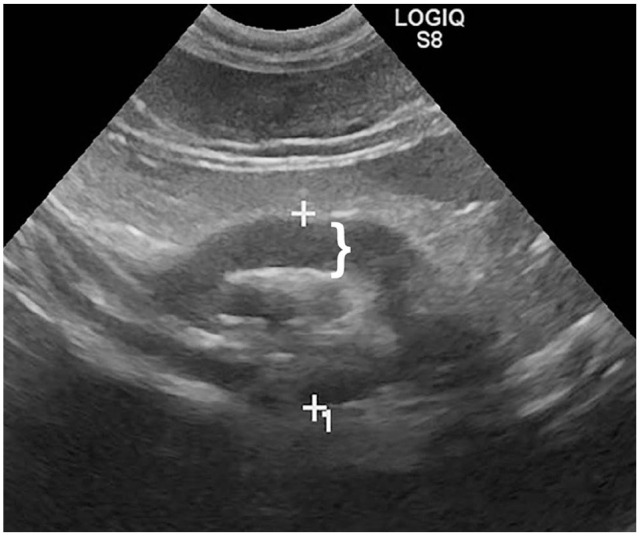

Case summary: A 2-year-old female spayed domestic shorthair cat was presented for evaluation of severe thickening of the proximal duodenum identified on abdominal ultrasound after a 1-year history of vomiting. At surgery, a proximal duodenal mass encompassed the areas of the major and minor duodenal papillae. A gastrojejunostomy was performed to bypass the proximal duodenum and maintain the integrity of the major duodenal papilla. Histopathology revealed changes consistent with feline eosinophilic sclerosing fibroplasia. The cat was treated with prednisolone and survived for 2.5 years. It was euthanized for bronchopneumonia.